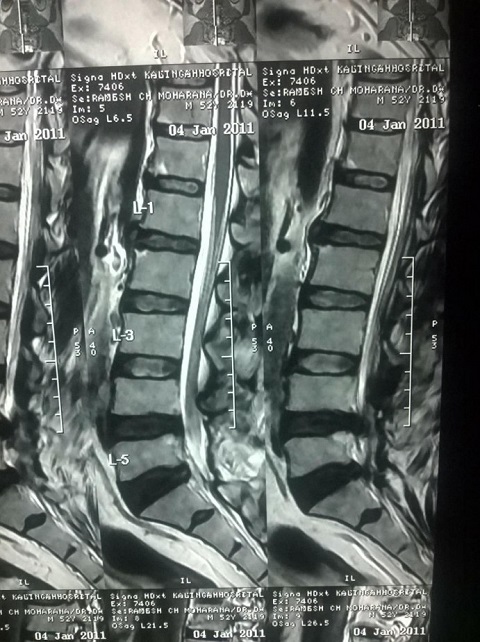

X-Ray of Ramesh Chandra Moharana